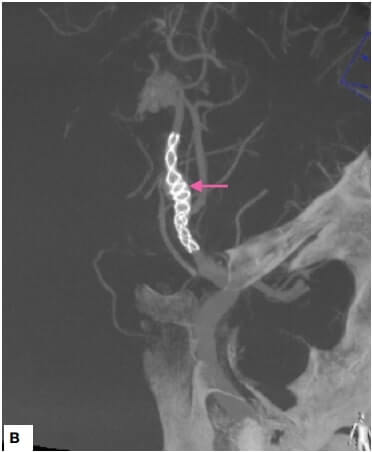

3D rotational angiogram image demonstrated a fusiform right A2-ACA aneurysm. Flow Diverter Stent (FDS) was used for the treatment of the cerebral aneurysm. Reconstructed VasoCT images demonstrated successful flow diverter placement across the aneurysm. The treatment was effective, and the intraprocedural check angiogram demonstrated flow stasis in the aneurysm.